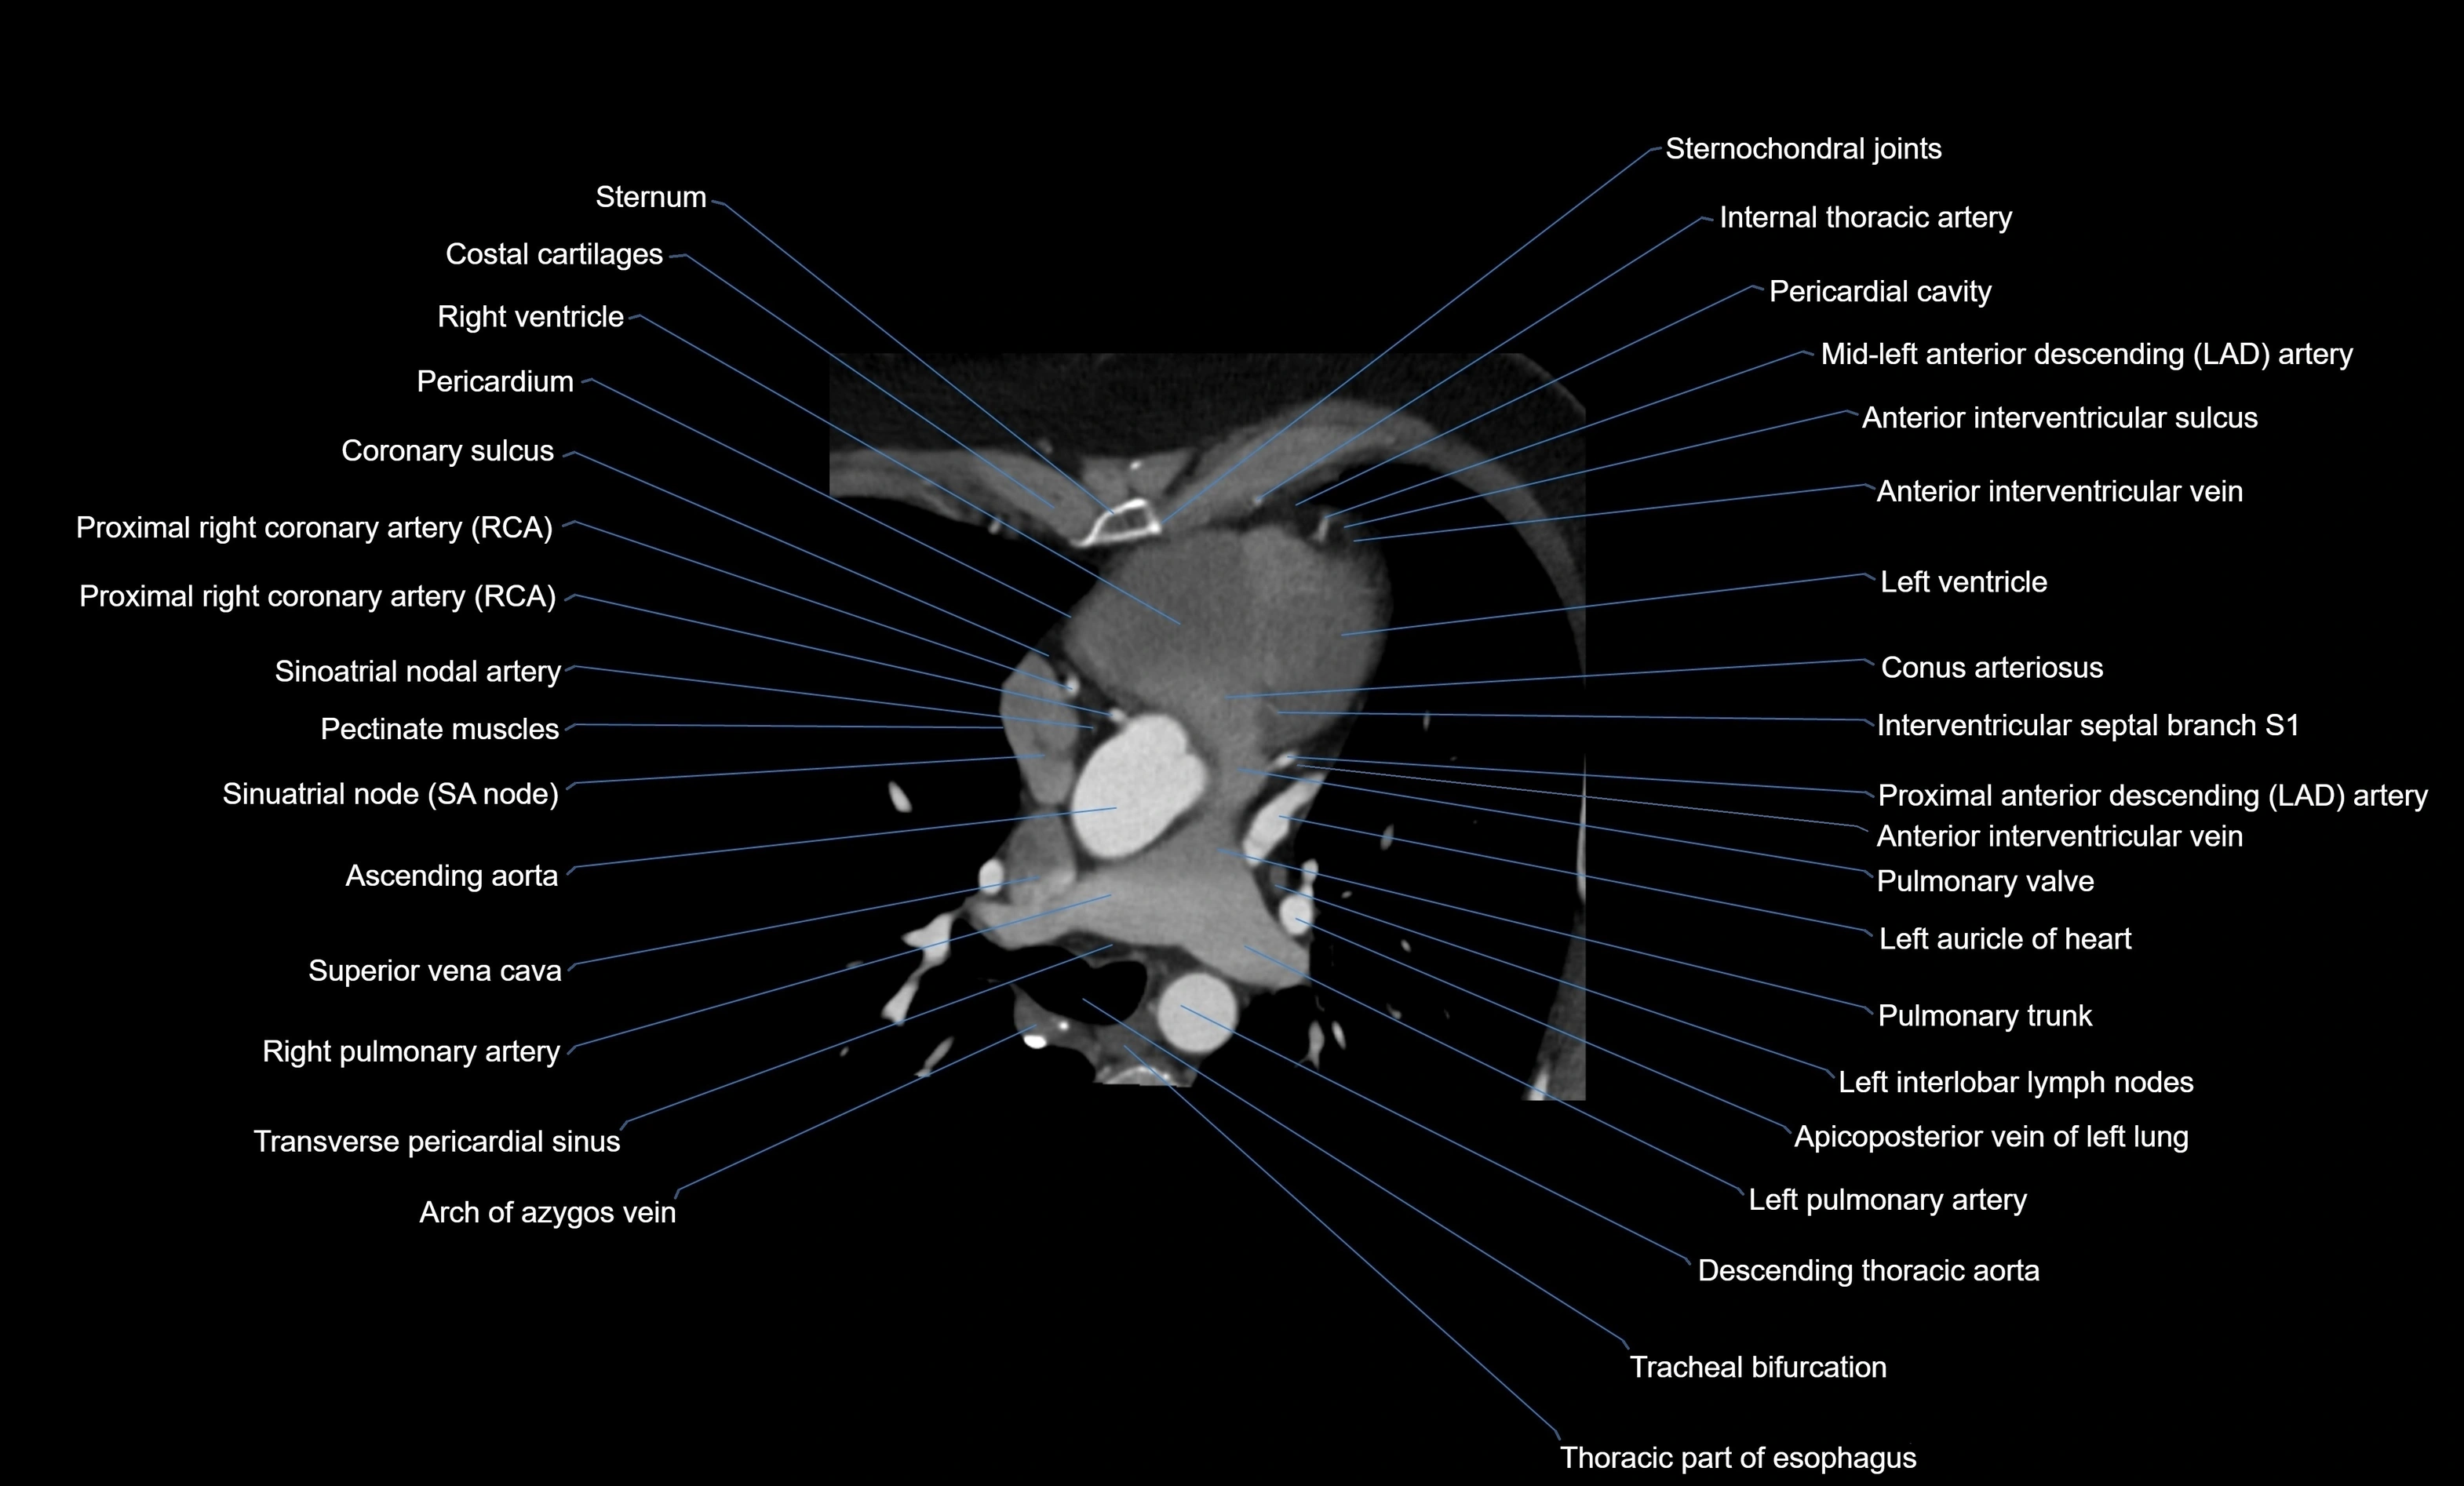

- Ascending aorta

- Conus arteriosus

- Interventricular septal branch S1

- Left anterior descending artery (LAD)

- Left auricle

- Left main coronary artery (LMCA)

- Left pulmonary artery

- Pectinate muscles

- Pulmonary trunk

- Pulmonary valve

- Right pulmonary artery

- Sinoatrial nodal artery

- Sinoatrial node (SA node)

- Superior vena cava

- Tracheal bifurcation

- Transverse pericardial sinus